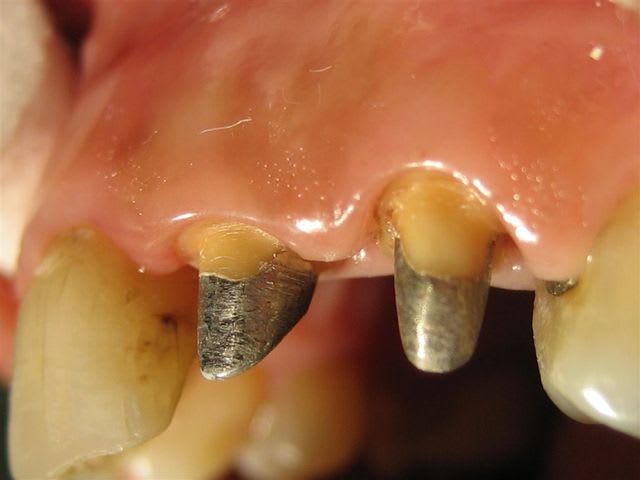

... un autre cas, mais ça ressemble toujours à ça >

Dans des teintes assez soutenues et peu translucides je trouve que la ccm avec ce type de joint rivalise bien avec les techniques plus "modernes"...